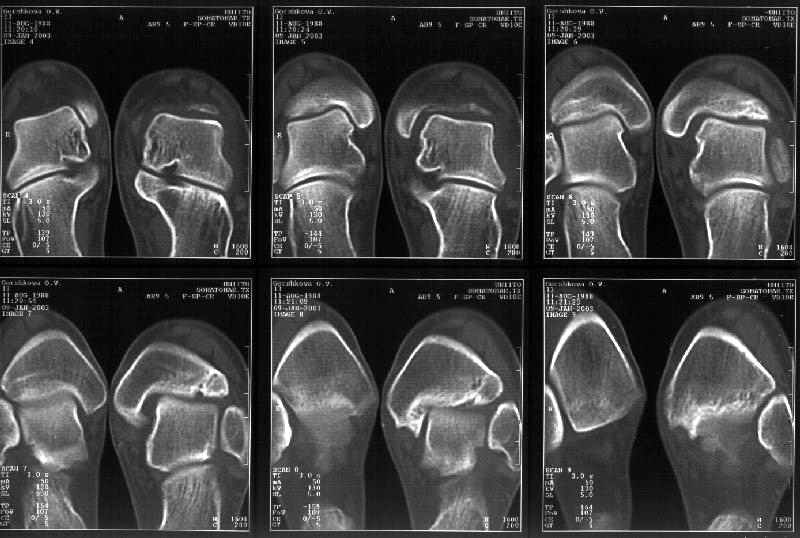

> тибиальной основы. По мне, КТ это совершенно ясно показывает.

Мне в тоже время совершенно ясно видно по той же КТ, по 4 срезам, расположенным в центре и вверху пленки, что перелома внутренней лодыжки не было, в следующем собщении я приложу увеличенный фрагмент томограммы. А к этому письму прилагаю увеличеный фрагмент послеоперационной рентгенограммы, где выделил отколотый фрагмент

позади внутренней лодыжки. И он, как я вижу, находится между стержнем и тараном. А перелома внутренней лодыжки, и тем более смещения, IMHO

не определяется.

Здесь 4 среза, начиная от основания лодыжки и проксимальнее. Где, по Вашему мнению, проходит линия перелома, отделяющая переднюю часть внутренней лодыжки от большеберцовой кости? Заранее спасибо.

Кликните для загрузки файла get_image.jpg

38KB (39385 bytes)

Я пометил линию перелома черной линией.

К сожалению на последних присланных срезах КТ нет более низкого, через таран, среза, который был на прежнем майле. На XR я попытался показать

стержень внутри сустава и то как он раскрывает пространство между тараном и мед. малеолом.